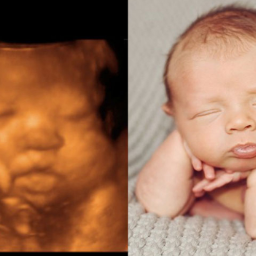

НЕМНОГО ИСТОРИИ: Несколько столетий назад, ученые наблюдая жизнь млекопитающих (т.е. существ кормящих молоком) до рождения, определили что до 8 недель от зачатия у существ природа которых - человек (т.е. у людей) полностью формируется органы и внешний облик, по которому можно без всяких экспертиз визуально определить со 100% уверенностью, что это существо человеческой природы.

Этот период жизни человека называли «эмбриональным периодом», а с 9-й недели и до рождения – «плодным периодом». Это термины, которыми описывается возрастной период жизни человека.

ВАША ЖИЗНЬ ДО РОЖДЕНИЯ!

Ваша жизнь до рождения! Такого вы еще не видели! Наука!